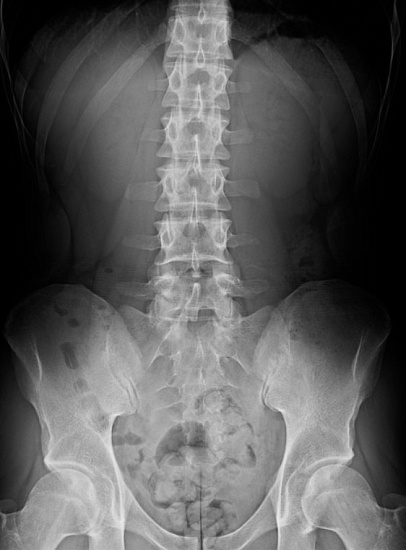

Рентгенография пояснично-крестцового отдела позвоночника – важный метод скринингового исследования, который позволяет оценить состояние пояснично-крестцового отдела позвоночника.

Диагностическая услуга выполняется в двух проекциях.